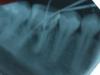

spirit Опубликовано 10 декабря, 2007 Поделиться Опубликовано 10 декабря, 2007 Обратилась пациентка с просьбой сохранить зуб. Лечение было начато в поликлинике. 36 зуб хронический гранулирующий периодонтит. Каналы хорошо проходимы. Сделали 6 сеансов внутриканального электрофореза. Зуб не выдерживает герметизма. Последний электрофорез сделали в пятницу, в каналы - крезофен на турундах, дентин повязка. В воскресенье появилось чувство "выросшего зуба", боль при накусывании. Пациентка самостоятельно убрала пломбу, делала содовые ванночки. Утром проснулась с отеком. Врач, который назначал лечение, сказал, удалять. Пациентка решила походить по частным клиникам.Я сомневаюсь, стоит ли браться за этот зуб. Смущает то, что при достаточно широких каналах с наличием экссудата в них, образовался отек мягких тканей. Ссылка на комментарий

Снежана Опубликовано 10 декабря, 2007 Поделиться Опубликовано 10 декабря, 2007 Киста на медиальном корне и бифуркация плохая, если пациентка молодая и очень хочет сохранить зуб, то можно попробовать, но заранее обговорить, что гарантию выздоровления на такой зуб давать сложно. Назначить курс антибактериальной и противовоспалительной терапии, а потом уже пробовать закрывать зуб, пойдет - ну и хорошо, а нет, так на удаление. Хотя я наверное за него не взялась бы. Ссылка на комментарий

Штаматолог Опубликовано 10 декабря, 2007 Поделиться Опубликовано 10 декабря, 2007 Киста на медиальном корне и бифуркация плохая, если пациентка молодая и очень хочет сохранить зуб, то можно попробовать, но заранее обговорить, что гарантию выздоровления на такой зуб давать сложно. Назначить курс антибактериальной и противовоспалительной терапии, а потом уже пробовать закрывать зуб, пойдет - ну и хорошо, а нет, так на удаление. Хотя я наверное за него не взялась бы. Снимок, конечно, недостаточно четкий, но думаю смысла нет за него бороться. Как восстанавливать будете? ВКВ+коронка? При такой бифуркации не сейчас если, так в скором времени получите из 1 зуба 2 , особенно если ВКВ делать. ЗЫ. Насчет кисты, пациентам простительно все подряд кистой обзывать, а докторам вроде не к лицу. По такому снимку плоховасто видно, но признаков кисты я лично не вижу. Ссылка на комментарий

annda Опубликовано 11 декабря, 2007 Поделиться Опубликовано 11 декабря, 2007 Обратилась пациентка с просьбой сохранить зуб. Лечение было начато в поликлинике. 36 зуб хронический гранулирующий периодонтит. Каналы хорошо проходимы. Сделали 6 сеансов внутриканального электрофореза. Зуб не выдерживает герметизма. Последний электрофорез сделали в пятницу, в каналы - крезофен на турундах, дентин повязка. В воскресенье появилось чувство "выросшего зуба", боль при накусывании. Пациентка самостоятельно убрала пломбу, делала содовые ванночки. Утром проснулась с отеком. Врач, который назначал лечение, сказал, удалять. Пациентка решила походить по частным клиникам. Я сомневаюсь, стоит ли браться за этот зуб. Смущает то, что при достаточно широких каналах с наличием экссудата в них, образовался отек мягких тканей. Главное противопоказание для эндодонтии-невозможность адекватного восстановления зуба(композитные памятники не рассматриваются.они станут именно надгробиями)Кисты не вижу,но бифуркация уже умерла. Ссылка на комментарий